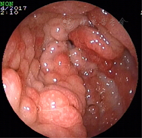

辅助检查:便常规+潜血:潜血阳性;血常规、凝血功能正常;难辨梭菌抗原及毒素检测阴性;血生化白蛋白30.4 g/L、钾3.02 mmol/L,余无明显异常;甲状腺功能T3、T4正常、促甲状腺激素(TSH)0.38 mU/L;结核干扰素测定正常;血清肿瘤标志物正常;血沉2 mm/1 h;CRP正常;类风湿因子(RF)101.9 kU/L;免疫球蛋白IgA、IgM、IgG正常,补体C3 0.672 g/L,补体C4 0.157 g/L;IgG亚类测定四项正常;抗核抗体(ANA)阴性;抗中性粒细胞胞浆抗体(ANCA)阴性;狼疮五项阴性;狼疮抗凝因子试验正常;心磷脂抗体正常;抗着丝点抗体阴性;腹部超声未见异常;甲状腺超声:甲状腺右叶实性结节;胸部CT:双侧胸腔少量积液;胃镜示胃底、胃体、胃窦弥漫性大小不等结节状息肉样隆起(图3),部分融合,表面充血水肿,以胃体、胃窦为重,胃底部可见黏膜下黑褐色素斑沉着(图4),十二指肠降部见散在小息肉样隆起;快速尿素酶法检测幽门螺杆菌阴性;胃窦、胃底、十二指肠降部取病理示慢性炎症;肠镜示回肠末端、盲肠、结肠、直肠广泛充血性息肉样隆起(图5),回肠、近端结肠息肉较小(直径0.1~0.2 cm),远端结肠、直肠息肉较大(直径0.2~0.4 cm)。病理示回肠慢性炎症,伴黏膜糜烂;盲肠增生性息肉,慢性炎症;直肠增生性息肉,慢性炎症,伴腺体囊状扩张。诊断:CCS。